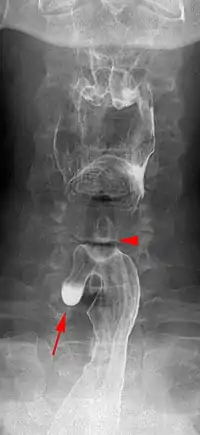

| Killian–Jamieson diverticulum. Arrowhead points at the closed upper esophageal sphincter, arrow points at the diverticulum partly filled with contrast medium. | |

A Killian–Jamieson diverticulum is an outpouching of the esophagus just below the upper esophageal sphincter.[1]

The physicians that first discovered the diverticulum were Gustav Killian and James Jamieson. Diverticula are seldom larger than 1.5 cm, and are less frequent than the similar Zenker's diverticula. As opposed to a Zenker's, which is typically a posterior and inferior outpouching from the esophagus, a Killian–Jamieson diverticulum is typically an anterolateral outpouching at the level of the C5-C6 vertebral bodies, due to a congenital weakness in the cervical esophagus between the oblique and transverse fibers of the cricopharyngeus muscle. It is usually smaller in size than a Zenker's diverticulum, and typically asymptomatic.[2] Although congenital, it is more commonly seen in elderly patients.[3]